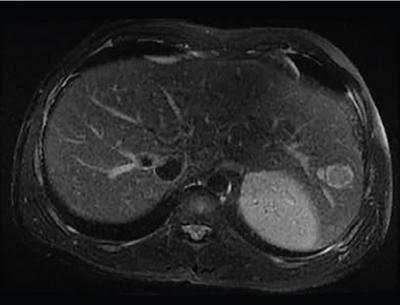

Shrinivas B. Desai, Ritu K. Kashikar, Shreya Shukla Radiological signs are classical and distinctive abnormalities characteristic of a disease. These can be seen on any imaging modality. Resemblance to commonly seen objects and patterns form the basis of radiological signs. The aim is to help the reader associate, understand and memorize these pathologies with the aid of signs. Various signs pertinent to hepatobiliary system are described in the chapter. Described on MRI when liver lesion shows a peripheral rim of high T2 signal intensity with the centre of the lesion appearing isointense to the background of noncirrhotic liver on T2WI mimicking an atoll. It is considered a characteristic sign of an inflammatory hepatic adenoma (image) but is only seen in about one-third of cases Extrinsic smooth impression over medial aspect of duodenum along its posteroinferior aspect, seen in pancreatic head pathologies like carcinoma. This sign is seen in pancreatic adenocarcinoma Presence of a persistently hyperattenuating dot within a lesion on arterial and portal venous CT. This corresponds with peripheral nodular enhancement seen on dynamic MR. Presence of bright dot suggests that the lesion is a hemangioma and helps in ruling out metastasis Ultrasound appearance of multiple cystic spaces or lesions that has been used to describe the appearance of an intraductal papillary mucinous neoplasm of the pancreas. Seen on contrast CT in portal hypertension. The appearance is based on resemblance to Medusa from Greek mythology. Dilated engorged paraumbilical veins radiating across umbilicus to join systemic veins is seen. This sign is seen in Caroli’s disease on contrast CT. Enhancing dots within dilated intrahepatic bile ducts represent portal radicles. Caroli’s disease Irregularly dilated pancreatic duct with multiple strictures and intervening dilatation with associated dilated side ductules resemble multiple lakes supplied by a single territory. Best seen in MRCP images. Chronic pancreatitis It is a finding on MRI and CT and is best seen on MRI T2-weighted and postcontrast T1-weighted sequences. Small necrotic/purulent areas in the pyogenic abscess ‘cluster’ together and then coalesce into a larger necrotic/purulent areas, eventually becoming a larger septated abscess cavity. At the periphery of these clusters: Associated with pyogenic hepatic abscesses and can help differentiate pyogenic abscesses from other types of liver lesions Abrupt termination of gas within the proximal colon at the level of radiological splenic flexure. The inflammatory exudates in pancreatitis extend to the phrenicocolic ligament giving rise to this sign Seen on grey scale ultrasound as a reverberation artifact when small calcific or highly reflective objects are imaged. The colour comet-tail artifact is an ultrasonographic sign seen in a number of situations when colour Doppler scanning is performed. This sign occurs in cases of traumatic right-sided diaphragmatic rupture with resultant partial herniation of liver through the defect. Separation of the herniated liver from its intra-abdominal component is via a small constriction at the level of diaphragm resembling a cottage loaf. Cottage loaf is a particular shape of bread in which larger and smaller roughly spherical balls are squashed together. Traumatic right-sided diaphragmatic rupture with resultant partial herniation of liver Bile eccentrically outlines luminal stone, creating a low attenuation crescent. Best seen on MRCP images. Choledocholithiasis Dilatation of both pancreatic duct and CBD is referred to as the double duct sign. Positive double duct sign suggests the diagnosis of carcinoma of the head of the pancreas and ampullary tumours and is hence considered ominous. Occasionally the sign may be seen in impacted gallstone in the distal duct. This feature is seen in patients with liver abscess on contrast-enhanced CT. A double, inner hyperattenuating and outer hypoattenuating rim is seen surrounding the hypodense abscess. The inner hyperattenuating rim corresponds to the enhancing abscess membrane, while the outer rim corresponds to the edema of the surrounding liver which appears hypodense and may show delayed enhancement. Liver abscess A positive duct penetrating sign is when a mass is penetrated by an unobstructed pancreatic duct; this makes focal pancreatitis the most likely cause rather than pancreatic carcinoma. This sign is best appreciated on MRCP (or ERCP). A radiographic sign that can be useful in differentiating between focal pancreatitis (inflammatory pancreatic mass) from pancreatic carcinoma. The duct-penetrating sign on MRCP is more helpful in differentiating between these two entities than a delayed enhancement pattern on CT or MRI It occurs when there is both limy bile and a gallstone in the common bile duct. The linear vertical radiopaque bile forms the line of the exclamation mark (i.e. !), whilst a more distal calculus forms the ‘dot’ at the end of the exclamation mark. Pathognomonic imaging sign of the rare diagnosis of limy bile on plain abdominal radiography Nonenhancing ruptured lesion with peripheral rim enhancement showing discontinuity from the rest of the liver and protruding from the liver surface is called the enucleation sign. Ruptured HCC Enlargement of the pericholecystic space. One of the signs of liver cirrhosis Can be seen on technetium 99m sulphur colloid scans of the liver and spleen, as well as CT studies. It occurs as a focal area of increased radiopharmaceutical uptake in the medial segment of the left hepatic lobe (segment IV) occurring as a result of SVC obstruction and portosystemic venous shunting between the superior vena cava and the left portal vein via the internal thoracic and paraumbilical veins. The equivalent of this sign may also be seen on contrast-enhanced CT scans as a hypervascular region. Budd–Chiari syndrome causes the hot spot sign in the caudate lobe

1) Atoll sign